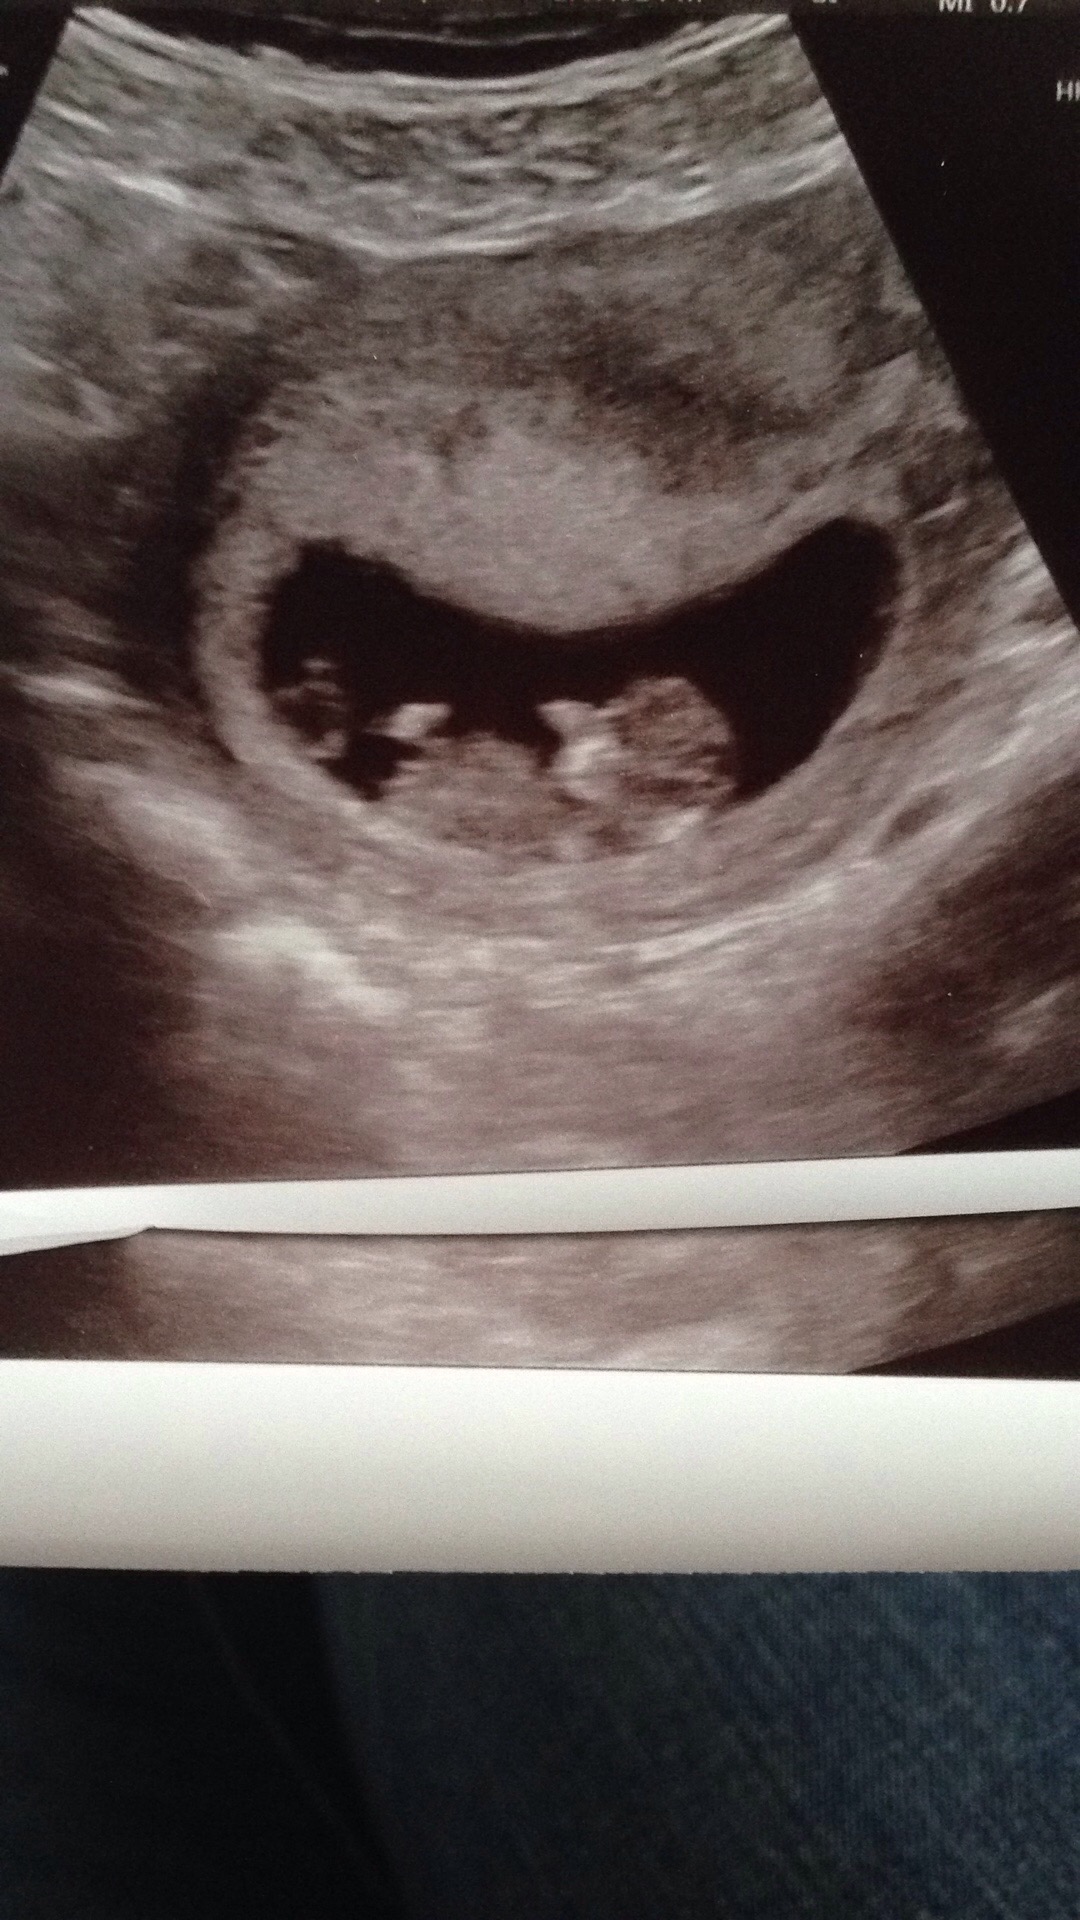

Had my first US today! Measuring only 6 weeks 5 days! So VERY early I know!

Heart rate was 138! It was a vaginal US so the ovum on the right of the photo is my right side!

Lemme know! Would love a blue bean.. I'm just happy I'm pregnant finally after trying so long!Attachment 35029